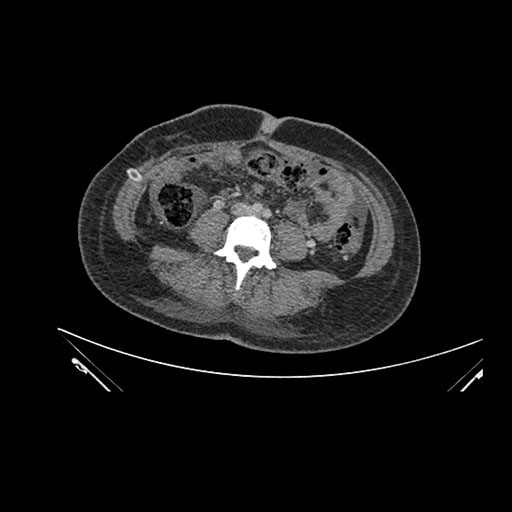

Axial Arterial

Axial Venous

Imaging analysis

Based on initial findings, which issue(s) would you be most concerned about?